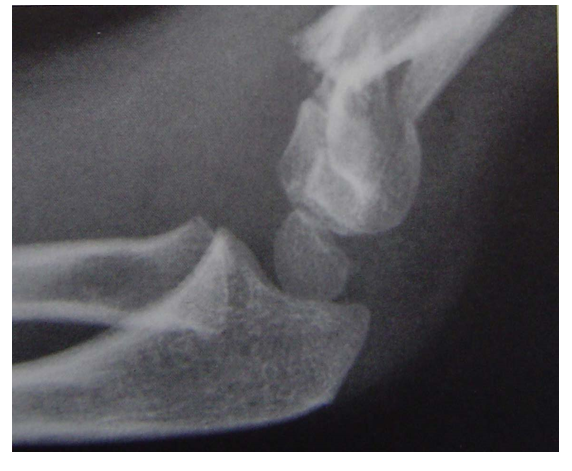

屈曲型复位方法

屈曲型伸直复位,伸直固定是方法之一。但石膏容易滑脱另一方法,伸直复位后屈曲肘关节,向后推挤维持复位,然后经皮克氏针固定。A、B术前x线片C 、D 手法复位 E 克氏针固定后